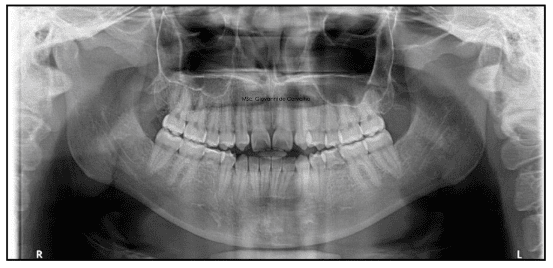

Durante a primeira avaliação, percebemos que Thaís tinha um perfil convexo, ou seja, o lábio inferior se projetava para frente, dando a sensação de que a boca estava sempre "forçando" o fechamento. Ela tinha todos os dentes permanentes, exceto os sisos, mas dois dentes importantes nunca se formaram: os incisivos laterais superiores. Além disso, mais tarde descobrimos também a ausência dos segundos pré-molares inferiores.

Sua mordida mostrava características típicas de Classe II, com dentes superiores inclinados para trás e uma mordida aberta de 2 mm, ou seja, os dentes da frente não se encontravam quando ela fechava a boca. Era um caso complexo, que exigia uma combinação de estratégias para devolver equilíbrio, estética e função.

No caso da Thaís, além dessa inversão da mordida, ela também apresentava ausência de alguns dentes permanentes (chamamos isso de agenesia) e mordida aberta, o que dificultava ainda mais a função mastigatória e a estética. Era um caso desafiador, mas que, com planejamento preciso e execução cuidadosa, trouxe um resultado transformador.